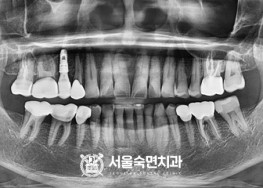

임플란트-치료-전후사진

서울대학교-출신-보건복지부-인증-통합치의학과-전문의-2인-책임관리